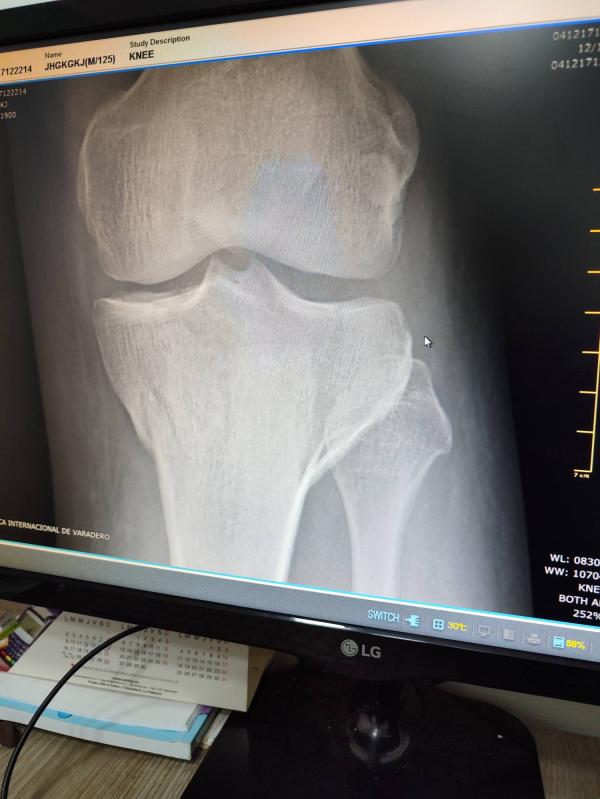

Муж бегая на пляже получил травму. Говорят, перелом, но мне кажется они перестраховываются. Девушки- врачи, что вы тут видите? Трещина?

Эх, отдых накрылся медным тазом, даже в туалет не может встать. Боль резкая при движении, в спокойном состоянии не болит

Ну если не может встать на ногу, конечно перелом. На снимке колено?